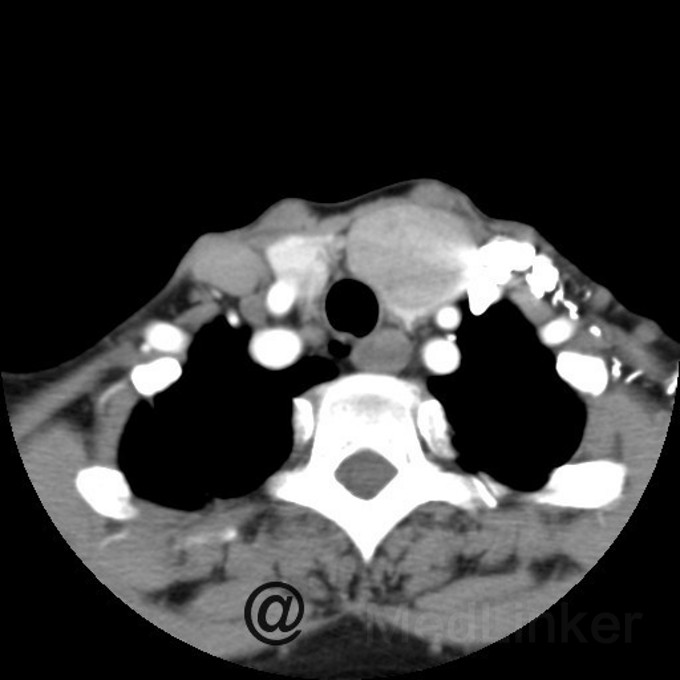

结节性甲状腺肿,发病率很高,有报道可达人群的4%。病因是由于患者长期处于缺碘或相对缺碘以及致甲状腺肿物质的环境中,引起甲状腺弥漫性肿大,病程较长后,滤泡上皮由普遍性增生转变为局灶性增生,部分区域则出现退行性变,最后由于长期的增生性病变和退行性病变反复交替,腺体内出现不同发展阶段的结节,有些结节甚至会恶变为甲状腺癌,那一般在什么时候干预才好呢?